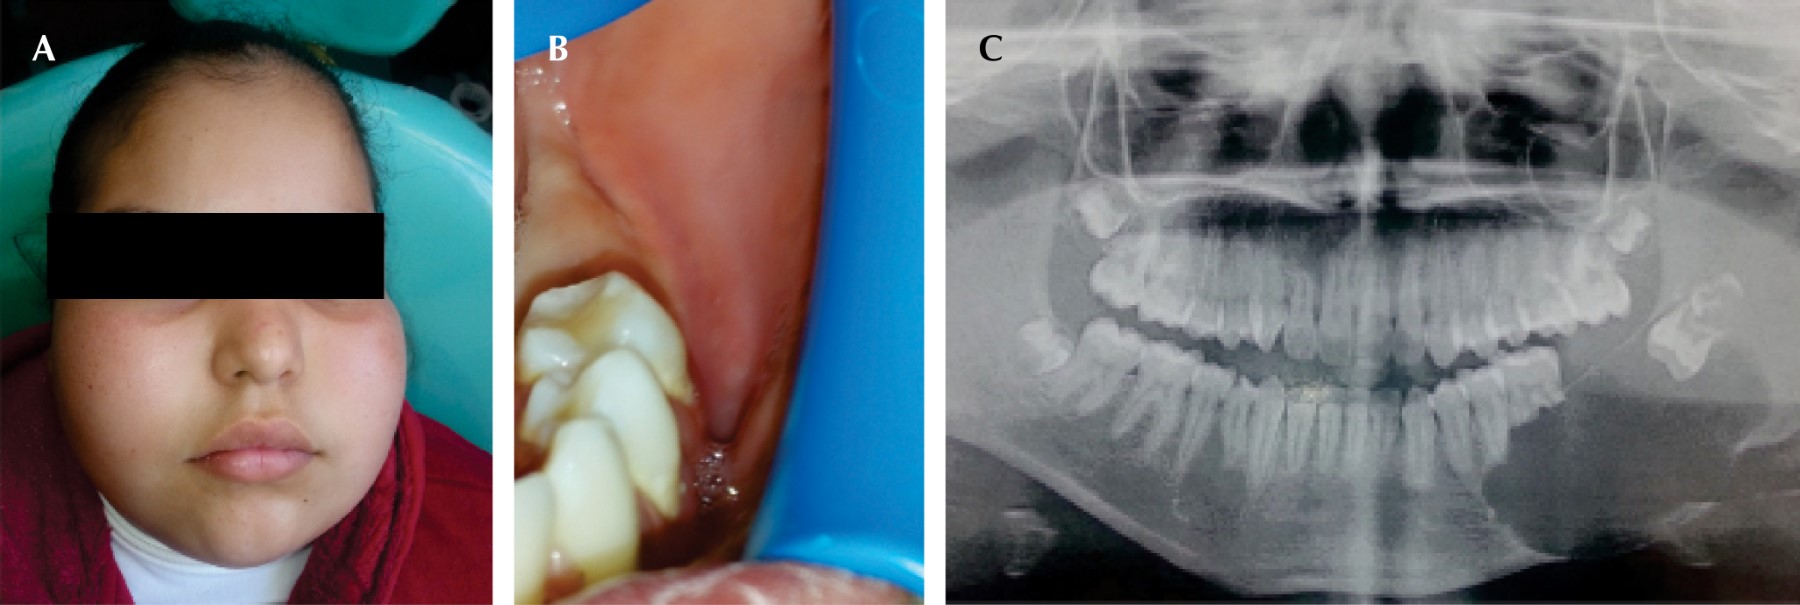

Se realizó enucleación, odontectomía y aspirado de la lesión intraluminal, con lo cual se obtuvo líquido de contenido amarillo seroso. Luego de la cirugía la paciente refirió parestesia en la región mentoniana de 2 × 0.5 cm y cuerpo de la mandíbula de 3 × 2 cm (Figura 2).

Los resultados de histopatología revelaron que el contenido líquido era de aspecto amarillo y turbio, se tiño con Papanicolaou, así como una hematoxilina y eosina para su interpretación y diagnóstico citológico, de donde se obtuvo como resultado "compatible con contenido de quiste de mandibular" y "alteraciones inflamatorias de tipo crónico en liquido quiste" (Figura 2). La citoquímica, antes de la centrifugación de líquido, demostró un aspecto hemorrágico y bacterioscópico negativo.

En la descripción macroscópica se mencionó lesión intraósea mandibular izquierda, contenido de múltiples fragmentos de tejido de forma irregular de 3 × 1.5 × 0.4 cm de color rojo vinoso y consistencia media. El diagnóstico fue ameloblastoma uniquístico con patrón plexiforme en hemimandíbula izquierda e inflamación crónica con tejido de granulación (Figura 2).